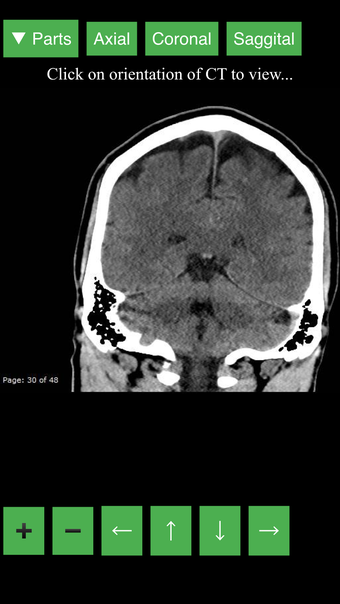

Radyoloji BT Görüntüleyicisi, doktorlar, tıp öğrencileri, radyoloji teknisyenleri ve diğer sağlık profesyonellerinin insan vücudu ve anatomisi hakkında daha fazla bilgi edinmelerine yardımcı olan faydalı bir araçtır. Uygulama, en önemli insan vücut parçalarının detaylı kesit çizimlerini içerir. Ayrıca, anatomiyi daha iyi görmek için görüntü etrafında döndürme, yakınlaştırma ve kamera hareket ettirme imkanı sunan etkileşimli bir 3D model içerir.

İnsan vücudu hakkında daha fazla bilgi edinmenize yardımcı olacak bir araç arıyorsanız, Radyoloji BT Görüntüleyicisi harika bir seçimdir. Detaylı çizimler ve etkileşimli bir 3D model içerir.